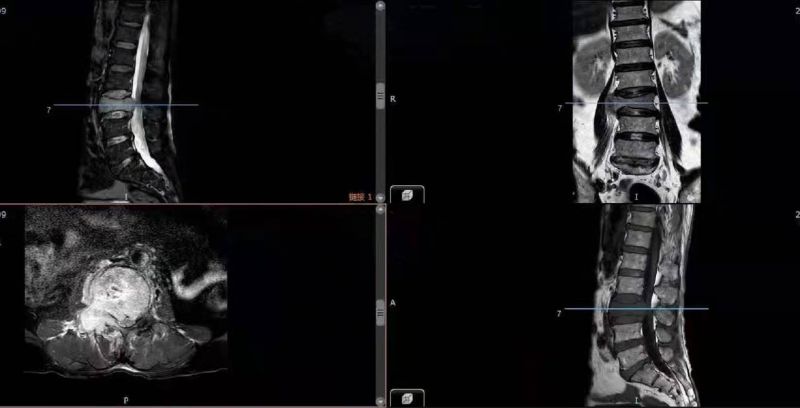

MRI显示:L3椎体被肿瘤完全破坏,右侧神经受压明显。